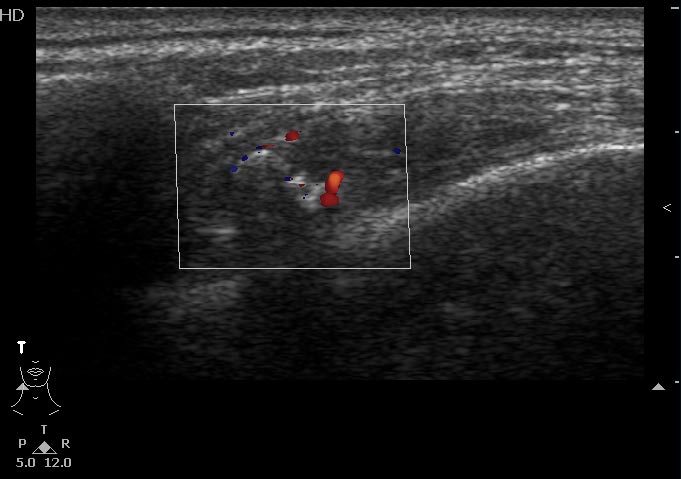

Мужчина 46 лет, жалуется на постоянные боли в правой височной области. В мягких тканях правой височной области пальпируется маленькое болезненное образование.

Сонограммы

Впервые встречаю подобное. Ваше мнение?

Ну вот деталь, которая может быть немаловажной - у пациента подагра, имеются тофусы в ушных раковинах.

На снимке утолщение веретенообразное мышечного слоя с наличием кальцификатов(два) Кальцификаты в мышце чаще встречаются при паразитарных инфекциях(трихиниллез,токсоплазмоз,цистецеркоз),но их больше по количеству и в разных местах.Оссифицирующий миозит-имеет свою картину и распространение.Насчет Хортона-навряд ли,это же поражение сосуда.Насчет тофусов-они содержат ураты,чаще локализуются подкожно(не в мышце),при подагре осификации вдоль сухожилий.А может был удар,гематома с частичной кальцификацией?

Если в анамнезе подагра, то тогда я за скопление солей уратов. Эта гадость может накапливаться где угодно, я сам видел и смотрел публикации коллег, когда это тофусы и в брюшной полости находили, а уж в мягких тканях, так это и подавно. Тем более что это болит, кальцинированная гематома не болела бы.